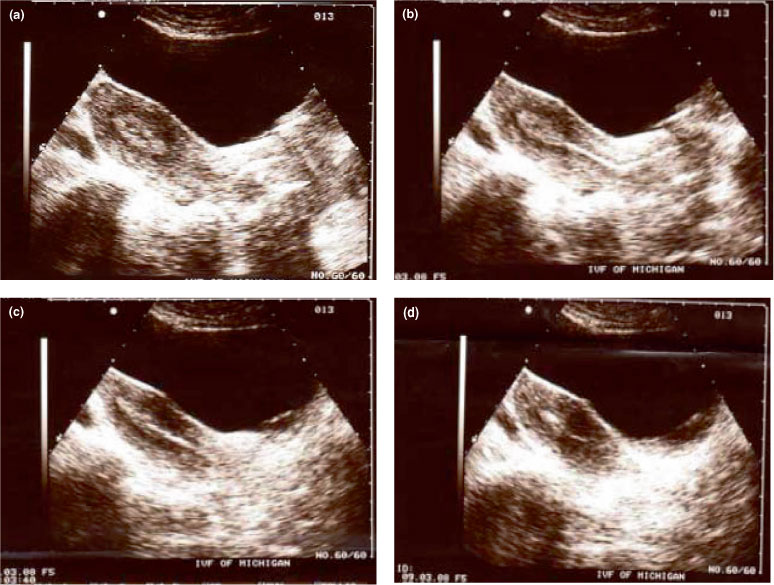

We identified 1268 first trimester ultrasound scans done at 6 (+1d) to 9 (+0d) weeks of gestation where gestational age at the day of the ultrasound could be precisely determined using the IVF dates . We calculated IVF dates by noting the number of days from fertilisation until the date of the ultrasound assessment .